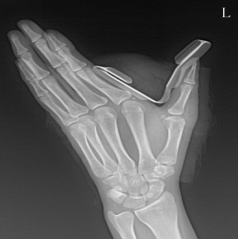

多指畸形

手足短骨解剖及常见疾病的影像学表现